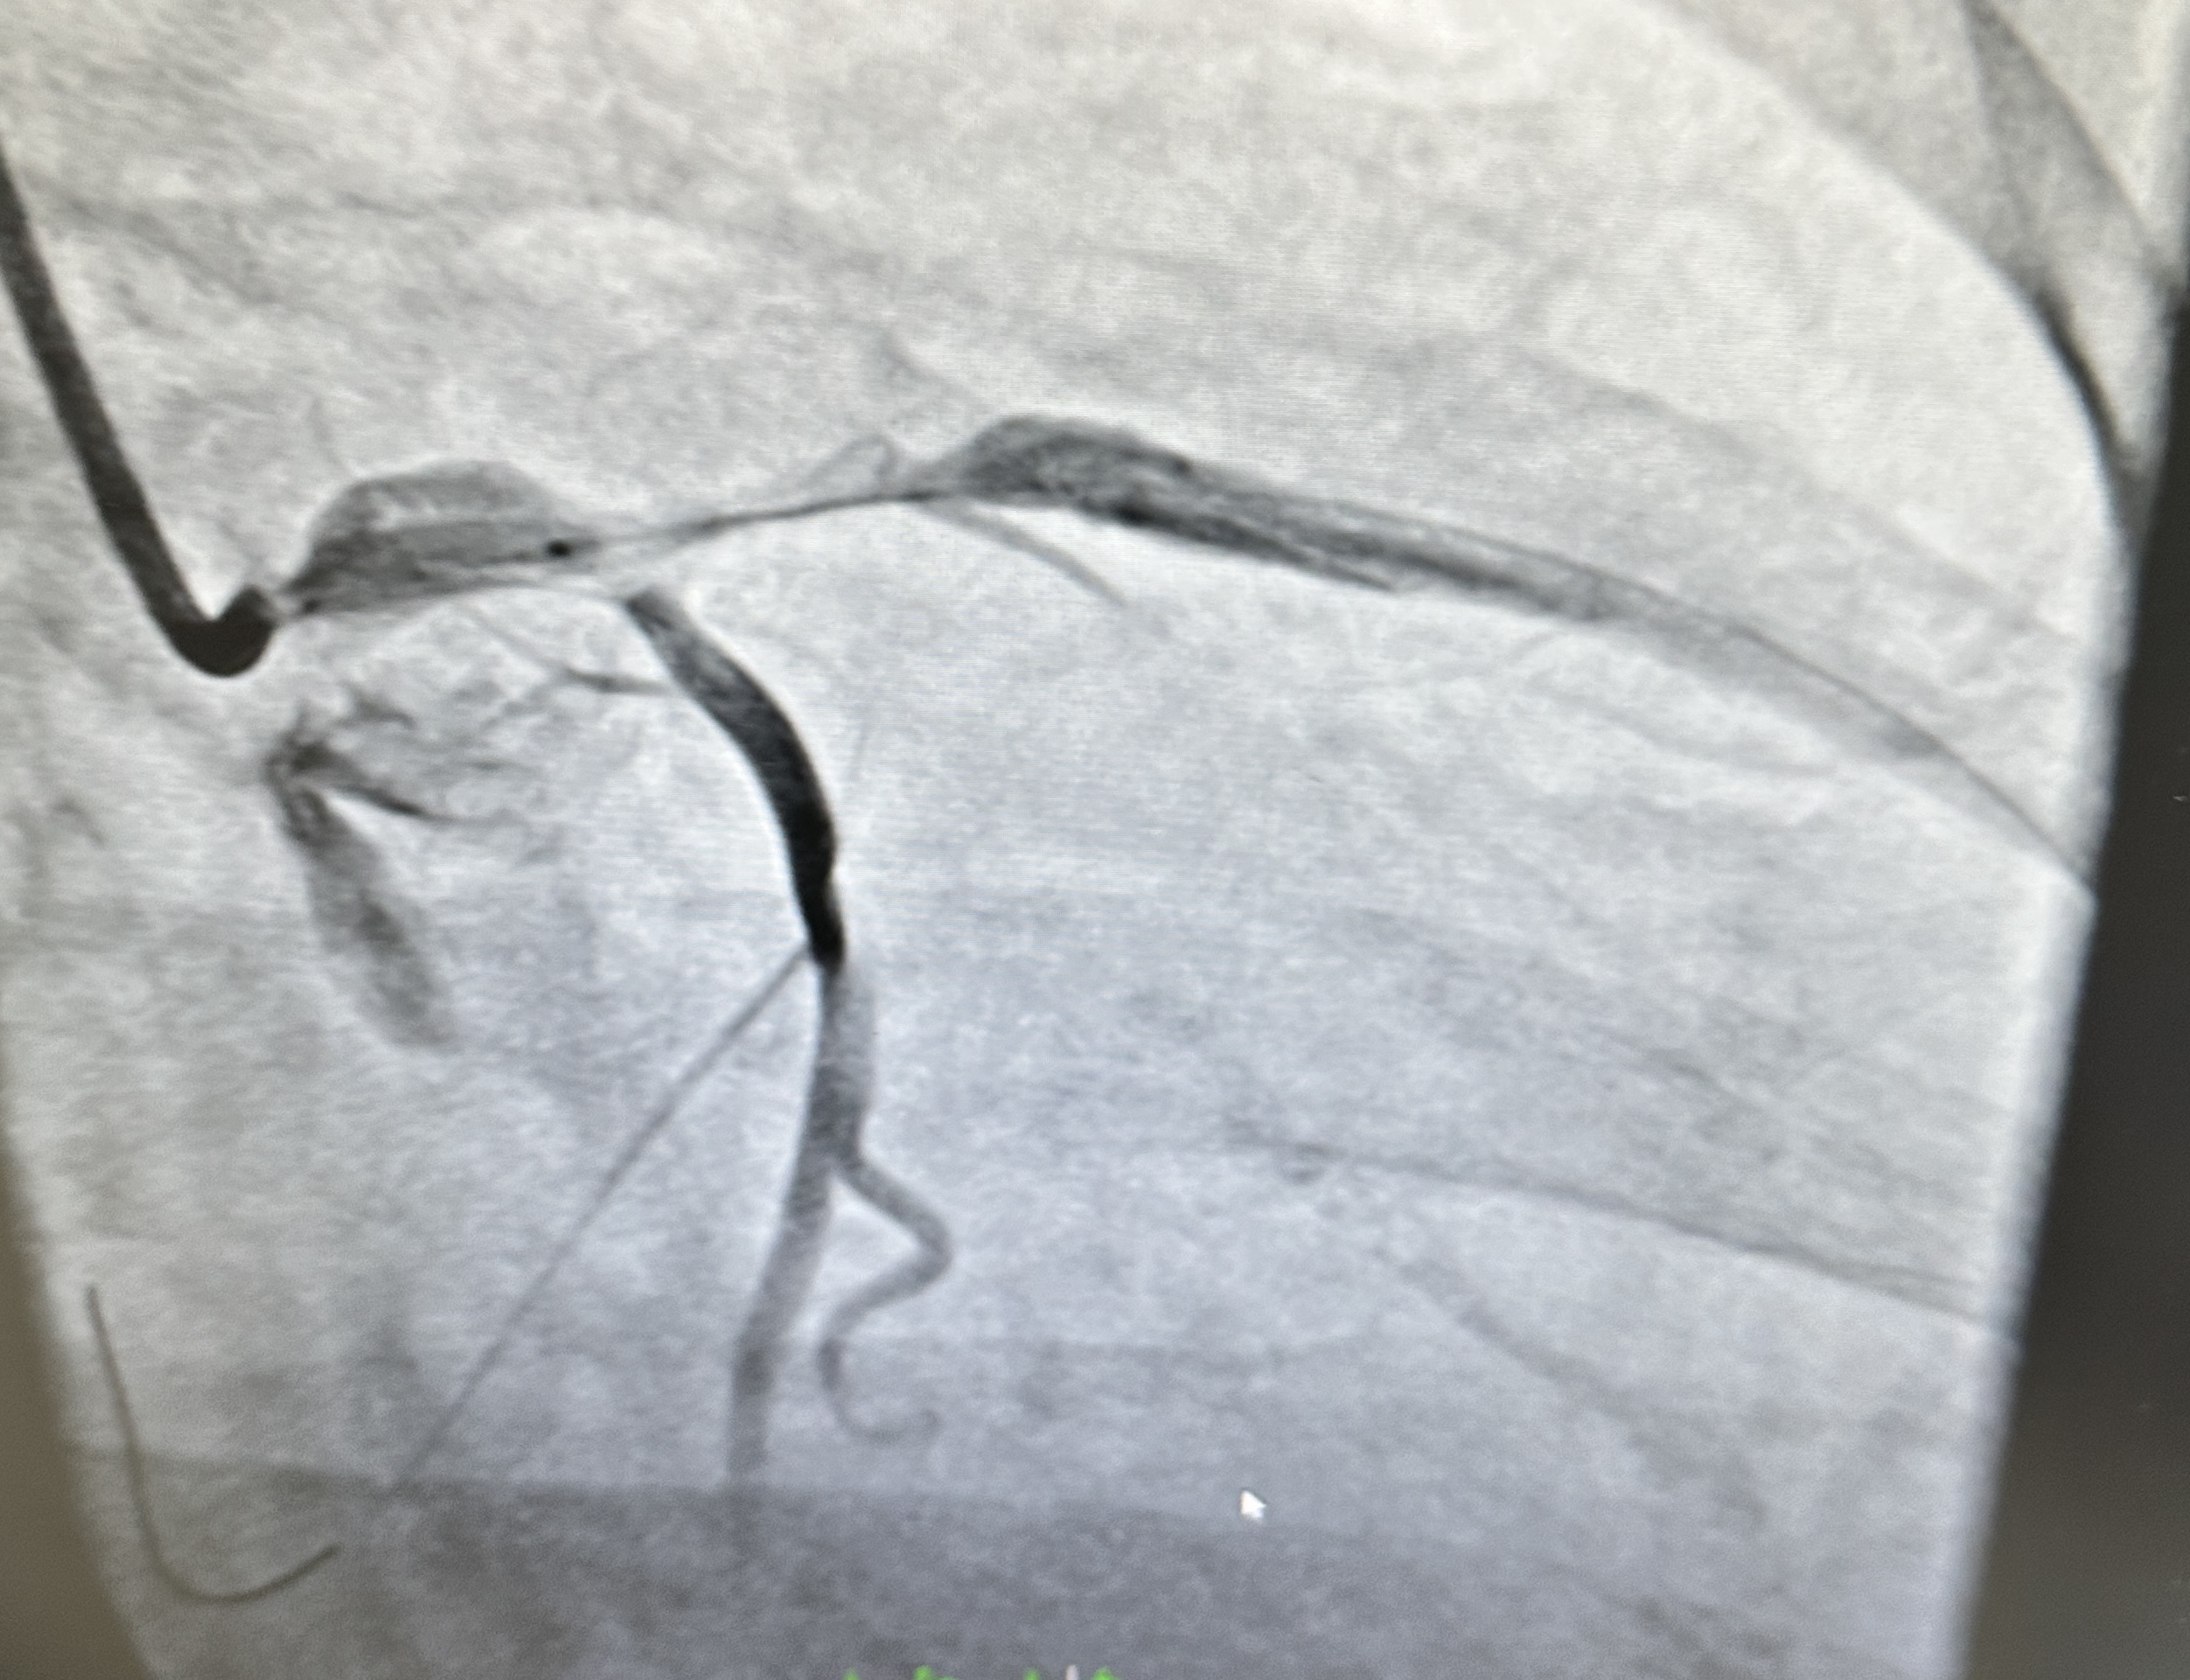

Right Coronary Artery (RCA): Dominance right. Large caliber, no significant stenosis. Angiographically normal with TIMI 3 flow. Left Main (LM): On first contrast injection afterJL engagement, mild ostial contrast staining was observed. On the second injection, there was more pronounced staining with dye hang-up, consistentwith catheter-induced LM dissection with suspectedpropagation toward the LAD/LCX.

- Actions: Stopped contrast injections; converted to RFA for stronger guide backup. Wired LAD and LCX in true lumen (confirmed by IVUS).

- Stenting: LM ¡æ LAD drug-eluting stent (DES) to seal LM entry; mini-TAP to LCX for ostial coverage.

- Imaging: IVUS pre-PCI confirmed dissection/intimal flap with intramural hematoma extending into proximal LAD/LCX; post-PCI showed good expansion/apposition, no residual entry.

- Final result: TIMI 3 flow in LAD and LCX; LM sealed; no residual flow-limiting dissection.